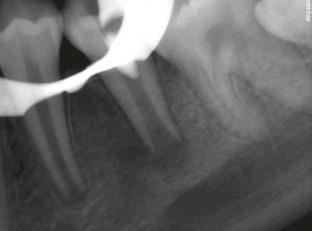

A 59-year-old male reported to the dental office with missing maxillary teeth due to poor oral hygiene. Treatment planning was done for all on four implant placements followed by prosthesis. A complete medical history was obtained and was negative for any significant medical problems. The patient denied being allergic to any medication as well. The patient agreed to the implant placement and was advised to have an orthopantomogram (Figure 1).

on the crest of the ridge in the region of teeth Nos. 15-25. While creating the incision, bleeding was noticed in the region of tooth No. 15 which intensified during the flap reflection (Figure 2). Bleeding was pulsatile, indicating an arterial bleed. Initially attempts to control bleeding included a pressure pack and ice pack, and the bleeder was isolated, and the vessel ligated (Figure 3). The bleeding could be controlled, and the procedure was completed by placing four Bioner implants (Bioner, Spain), size 4/10 mm. Sutures were placed, and patient was kept on basic medication for pain and infection control. Immediately after the surgery, the patient was advised to get a CBCT. As shown in Figure 4, a coronal view and Figure 4B (yellow arrows), the position of the artery can be seen.

Figure 1: Pre-op panoramic radiograph Figure 2 (left): Alveolar antral artery (AAA). Figure 3 (center): The artery has been ligated with suture. Figures 4A and 4B (right): CBCT post-implant placement and position of the artery coronally (top). 4B. Showing the position of alveolar antral artery (AAA) in relation to implant placement as indicated by the yellow arrows (bottom)